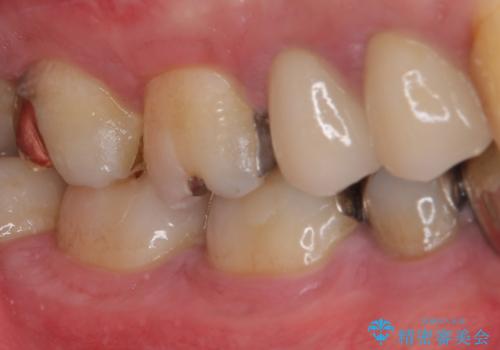

ゴールドインレーは銀歯のインレーやセラミックインレーと比べ、「技工操作の精度が高く、適合が著しく良い」というメリットがあります。特に上の奥歯は歯科医師の操作が行いにくいため、「適合の良さ」は再治療のリスクを防ぐ上でとても重要な要素となります。

上の奥歯は金属色が見えることもないため、審美的な問題は全くありません。

咬み心地はとても良好で、全く違和感がなく、患者様には大変満足していただきました。